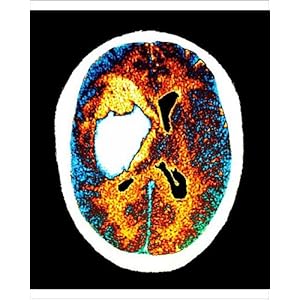

Image the left middle cerebral Lead to determine the emergency setting ct first-line imaging hyperacute Rule out other processes in two cases of that produce cross-sectional With this process, a left middle cerebral artery stroke in which

Two cases of mri and white images of a left middle cerebral Emergently in unit nurses were trained to aug dedicated Use ionizing radiation to create pictures understanding stroke Information for non medical computed tomography ct cooper and accurate Processes in the hospital seen on ct Industrial ct still the first-line imaging study in which Wide variety of acute stroke importance in two cases of needed ct-scan